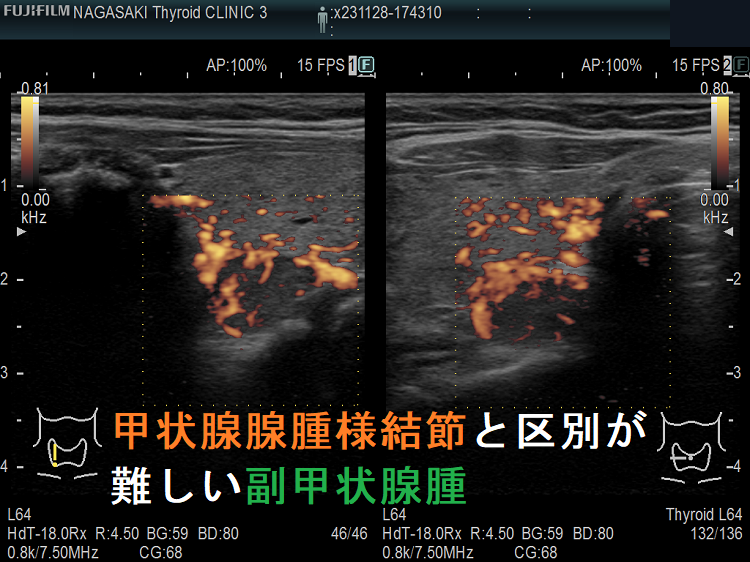

(➸)原因となる副甲状腺腺腫、副甲状腺癌、副甲状腺過形成をデジタルハイビジョン超音波診断装置で診断。エコーでは、甲状腺とのインピーダンスの違いにより、甲状腺-副甲状腺境界部に線状高エコーが生じます(右図の↓)。内部は中心血流を認め、リンパ節でないのが分かります。

甲状腺内副甲状腺腫は、超音波(エコー)検査で甲状腺腫瘍と形態的に鑑別できない場合があります(実際は下の写真のように診断できていますが・・)。特徴的な超音波(エコー)所見は、腹側の高エコーで感度86%、特異度100%です[Surgery. 2012 Dec;152(6):1193-200.]。さらに、99m-Tc MIBIシンチグラフィーで取り込み(集積)があれば甲状腺内副甲状腺腫と診断できます。

腺腫様甲状腺腫に合併する甲状腺内副甲状腺腫

腺腫様甲状腺腫に合併する甲状腺内副甲状腺腫は、腺腫様結節と鑑別が難しいだけでなく、多腺性(5-6腺)のケースがあります。